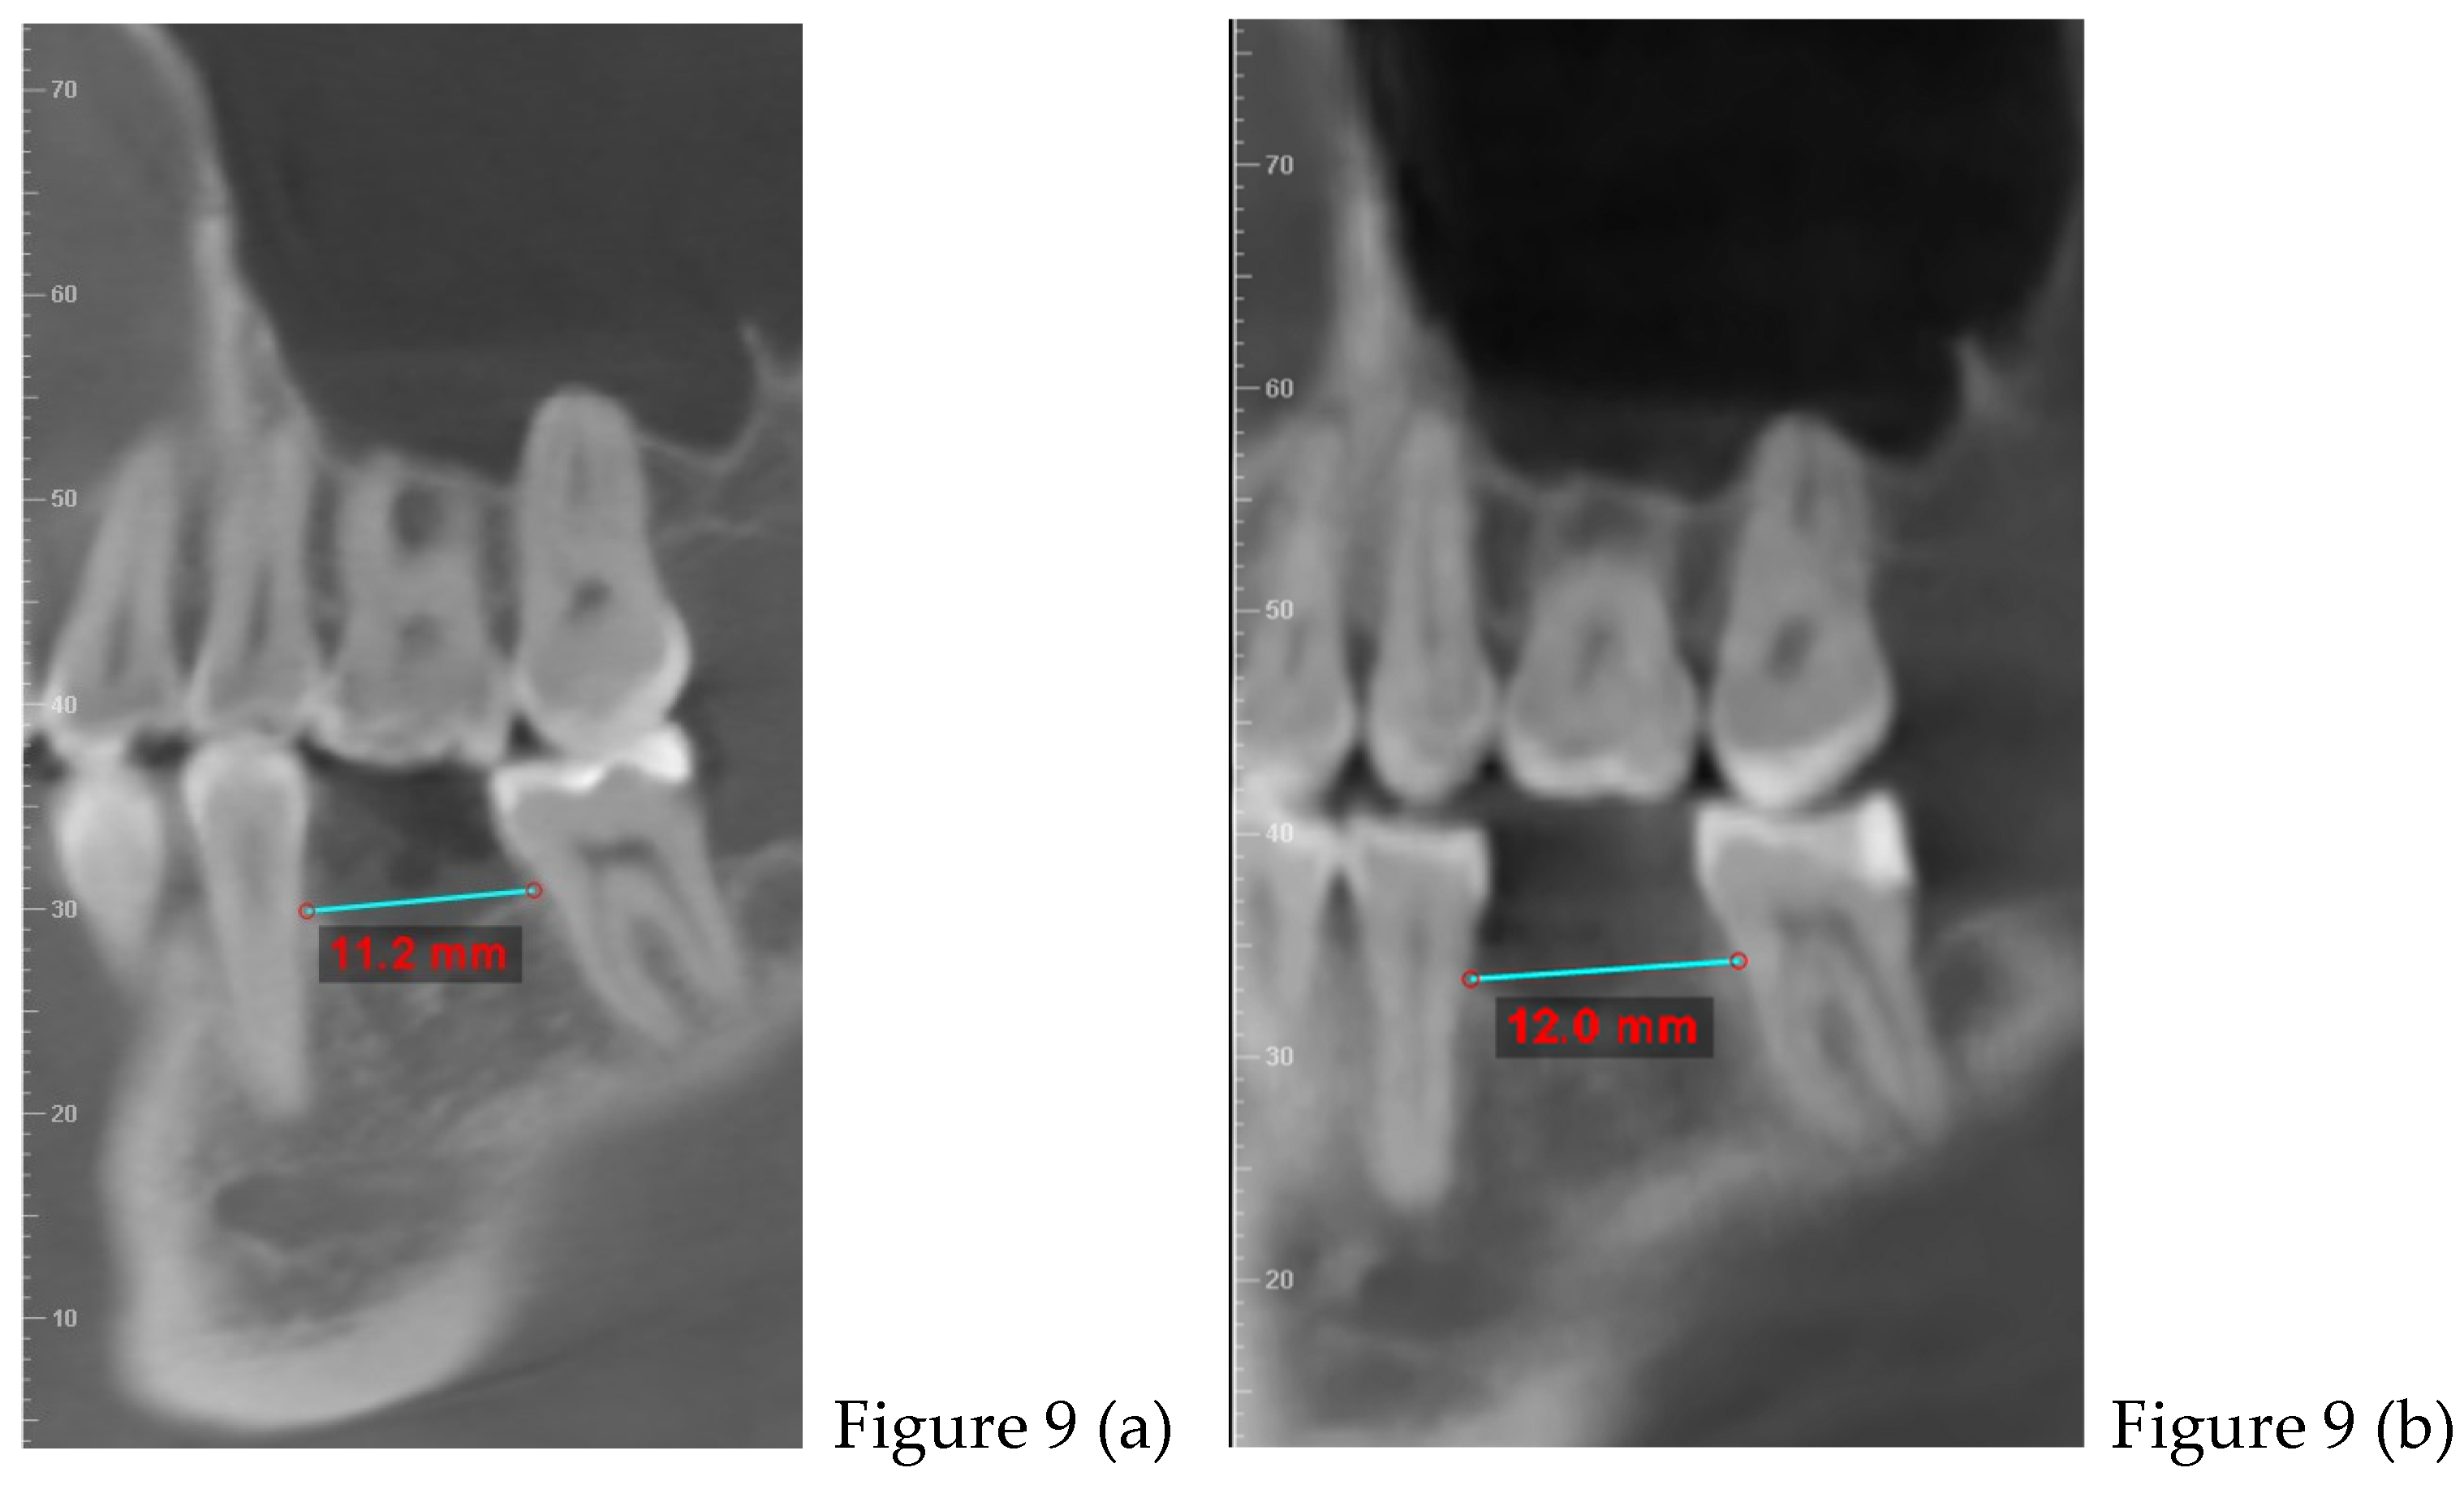

2.2. Cone Beam CT Analysis

| CBCT (t0) | |

| after 8 months | Retainers + CBCT (t1) + final photos |